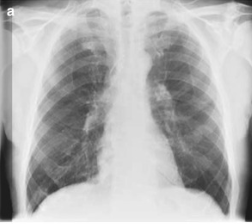

Pneumonia

Among febrile neutropenic patients with a “normal” chest x-ray,

up to 60% of patients may have findings of pneumonia on CT

Common CT findings

Bronchoscopy